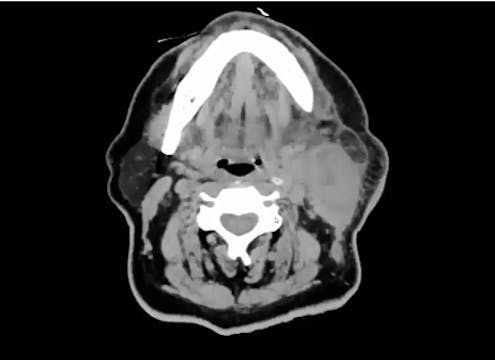

06/27/2022- Dr. David Sher - Radiation Oncology - Head & Neck

Chartrounds US - Head and Neck Cancer

palliative RT